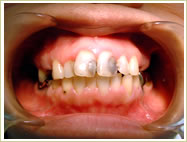

60歳 男性 インプラント埋入数:6本 画像拡大

治療前 治療後

治療後 治療後 治療後